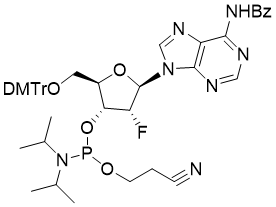

馬鞍山致研生物醫(yī)藥科技有限公司成立于馬鞍山市鄭浦港新區(qū)現(xiàn)代產(chǎn)業(yè)園。公司專(zhuān)注于生物小分子、醫(yī)藥中間體相關(guān)產(chǎn)品的研發(fā)和生產(chǎn),產(chǎn)品主要包括DNA亞磷酰胺單體、RNA亞磷酰胺單體、特殊單體以及按照客戶(hù)要求定制的RNA和DNA,并且公司提供定制合成等方面的研究服...

馬鞍山致研生物醫(yī)藥科技有限公司成立于馬鞍山市鄭浦港新區(qū)現(xiàn)代產(chǎn)業(yè)園。公司專(zhuān)注于生物小分子、醫(yī)藥中間體相關(guān)產(chǎn)品的研發(fā)和生產(chǎn),產(chǎn)品主要包括DNA亞磷酰胺單體、RNA亞磷酰胺單體、特殊單體以及按照客戶(hù)要求定制的RNA和DNA,并且公司提供定制合成等方面的研究服...